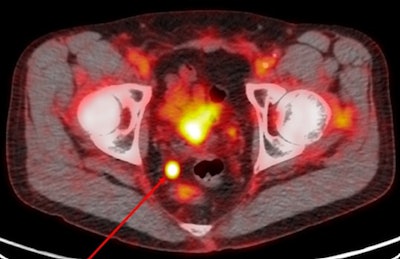

Pylarify is labeled with F-18 and homes in on PSMA, a protein that is overexpressed on the surface of more than 90% of both primary and metastatic prostate cancer cells, according to the company. PET imaging can detect accumulations of the agent at sites of prostate cancer, making Pylarify useful for detecting metastasis from primary cancer or recurrence of disease in men who have already been treated.

PSMA is expressed in 90% of prostate cancers, and Pylarify binds to targets to enable PET detection. The F-18 tracer used with the radiopharmaceutical is produced in cyclotrons and has a 110-minute half-life, which Lantheus said allows for wider geographic distribution.